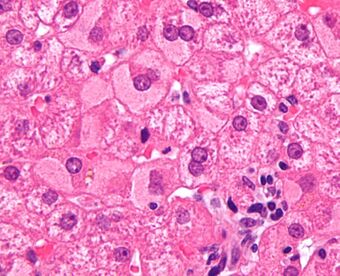

Micrograph showing ground glass hepatocytes, which are seen in chronic hepatitis B infections (a type of viral hepatitis), and represent accumulations of viral antigen in the endoplasmic reticulum. H&E stain.